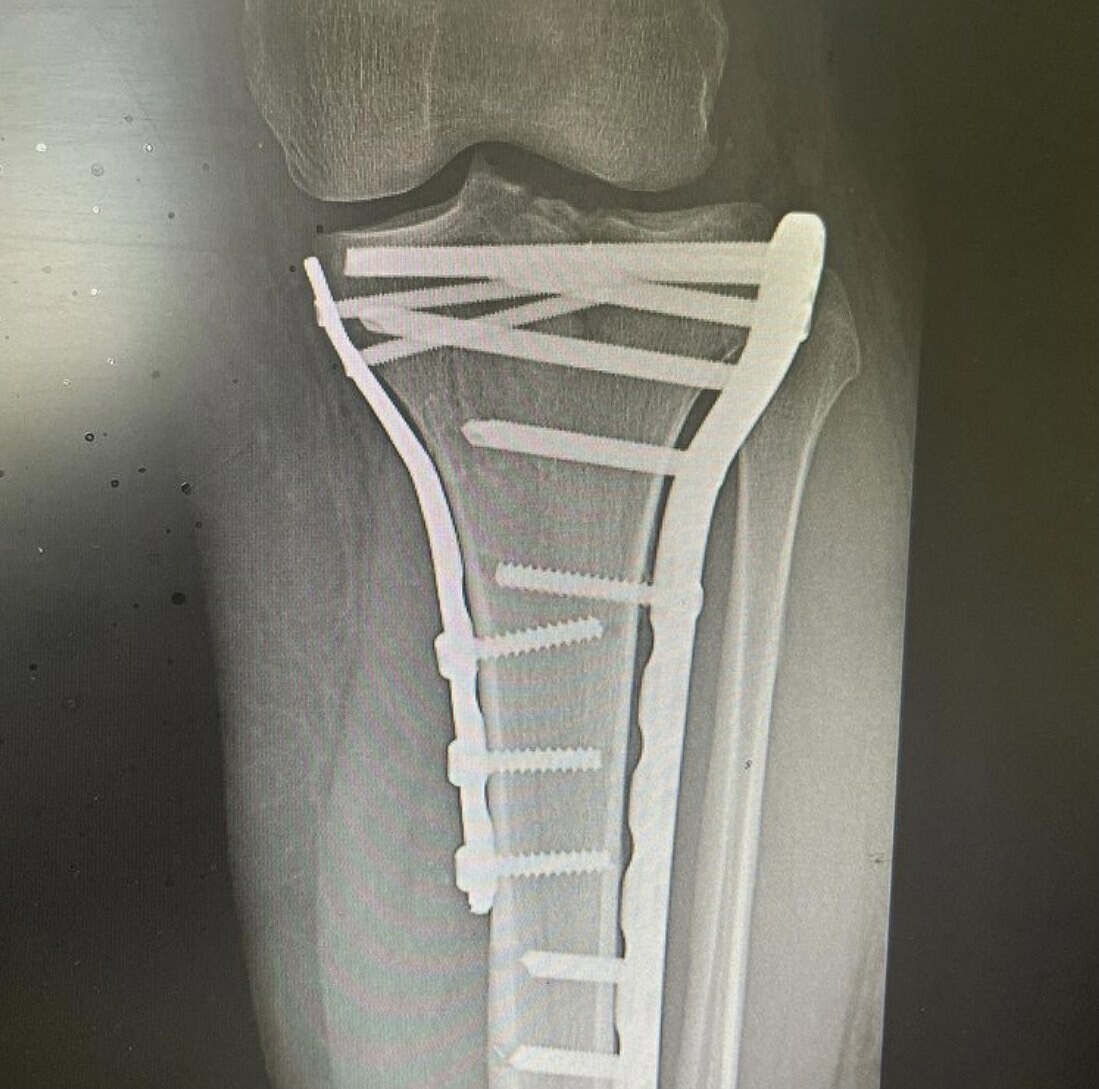

Врачи обнаружили у мужчины многооскольчатый перелом верхнего суставного конца большеберцовой кости с разрывом боковых связок.

Фото: Telegram-канал «Травматология и ортопедия Татарстана»